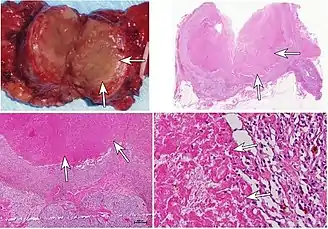

Macroscopic

The macroscopic appearance of an area of coagulative necrosis is a pale segment of tissue contrasting against surrounding well vascularized tissue and is dry on cut surface. The tissue may later turn red due to inflammatory response. The surrounding surviving cells can aid in regeneration of the affected tissue unless they are stable or permanent.

Microscopic

Microscopically, coagulative necrosis causes cells to appear to have the same outline, but no nuclei.[2] The nucleus is lost and there is cytoplasmic hypereosinophilia on H&E stain.[4] Also, it is characteristic of coagulative necrosis to not have a zone in between necrotic cells and viable cells. There is an instant transition, lacking granulation tissue in between.[5]